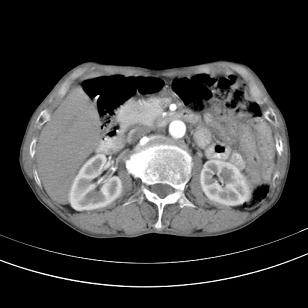

标题: 男,65岁,反复右上腹痛, [打印本页]

标题: 男,65岁,反复右上腹痛,

胃镜提示十二指肠占位